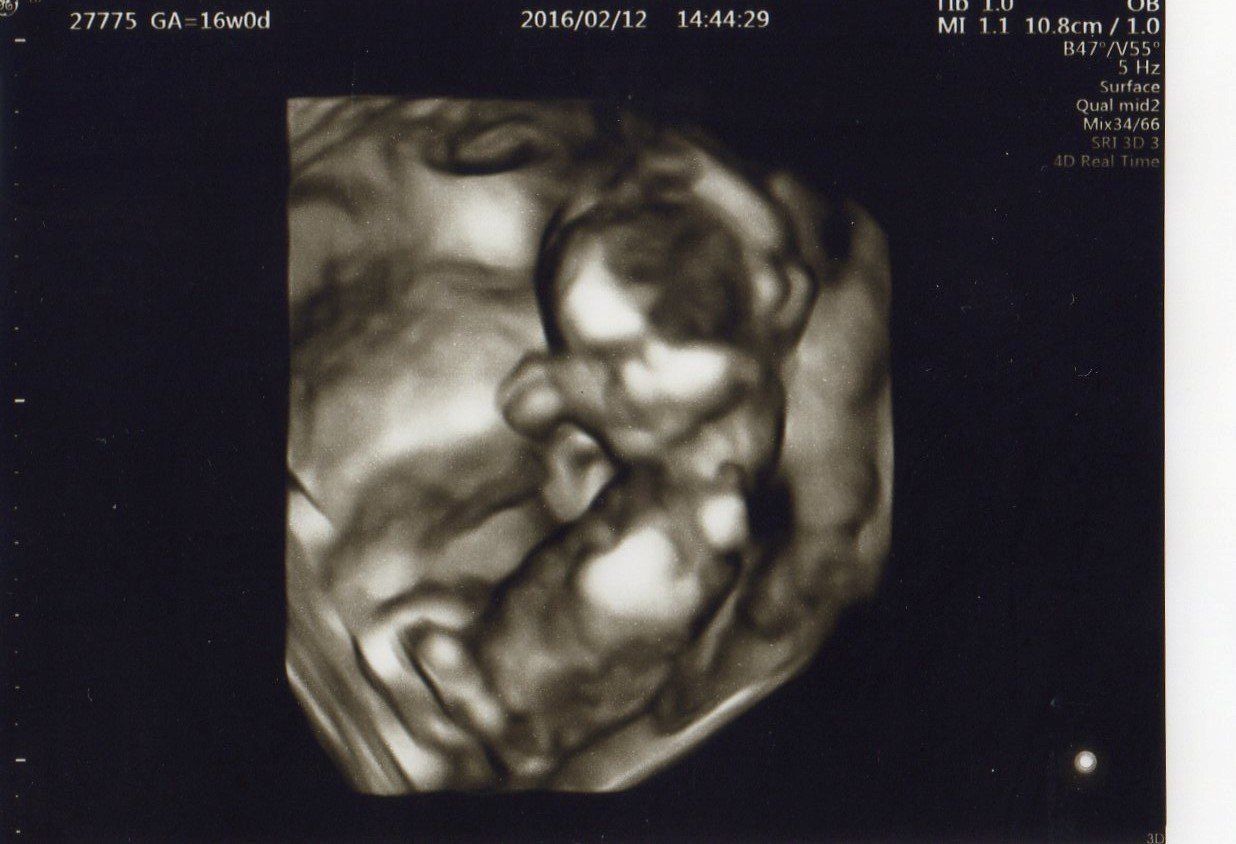

妊娠16週目 かわいらしい顔が見えました

妊娠16週目。エコー写真上部から順に、頭・首・体が見えます。3Dで顔の目・鼻・口がはっきり確認できるほど成長しました。かなり人間らしい姿で、大きくなった様子が分かります。

こちらへ顔を向けて、左手で「Good!」と親指を立てている姿に夫婦で爆笑。この頃から安定期に入り、おなかもぽっこり大きくなりました。